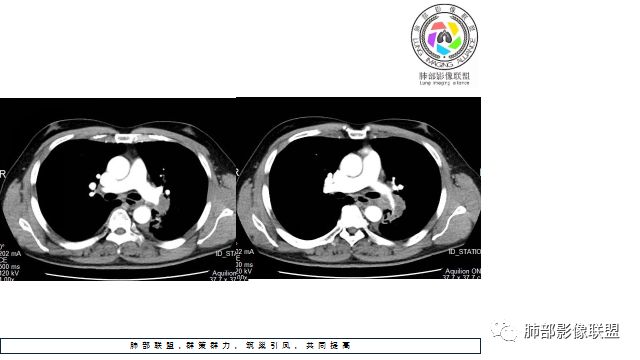

1.左下肺门区巨大肿块,支气管显示不清,轻度阻塞性炎症,没有明显肺不张,提示管腔受压狭窄可能性大于堵塞,这较少见于鳞癌。

2.病灶边缘光滑,未见明显分叶、毛刺,未见明显强化,这符合腺癌影像学特点,却符合神经内分泌癌表现。

3.病灶内密度均匀,轻到中度均匀强化,大病灶未见明显液化坏死区及空洞,不符合鳞癌而符合小细胞肺癌特点。

4.病灶内有肺动脉走形,血管局部受压,未见破坏,病灶乏血供,呈血管包埋或血管造影征;侵袭性力强及破坏力弱、血管漂浮都符合SCLC,所以鳞癌的可能性也不大。

5.左肺门块影或淋巴结肿大,竭力挤兑肺门血管结构,呈冰冻肺门;有时候SCLC可以单独呈现冰冻肺门,而没有没有冰冻纵隔。